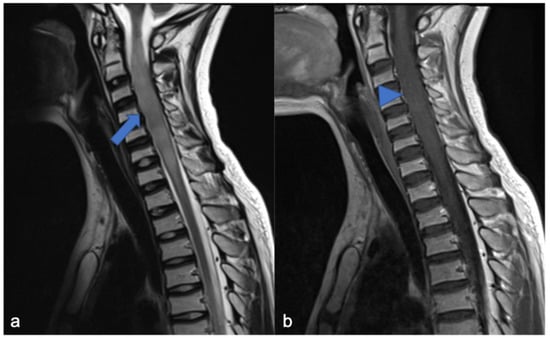

3. Ependymomas

- Ghasemi, D.R.; Sill, M.; Okonechnikov, K.; Korshunov, A.; Yip, S.; Schutz, P.W.; Scheie, D.; Kruse, A.; Harter, P.N.; Kastelan, M.; et al. MYCN amplification drives an aggressive form of spinal ependymoma. Acta Neuropathol. 2019, 138, 1075–1089. [Google Scholar] [CrossRef]

- Swanson, A.A.; Raghunathan, A.; Jenkins, R.B.; Messing-Jünger, M.; Pietsch, T.; Clarke, M.J.; Kaufmann, T.J.; Giannini, C. Spinal Cord ependymomas with MYCN amplification show aggressive clinical behavior. J. Neuropathol. Exp. Neurol. 2019, 78, 791–797. [Google Scholar] [CrossRef]

- Wippold, F.J.; Smirniotopoulos, J.G.; Moran, C.J.; Suojanen, J.N.; Vollmer, D.G. MR imaging of myxopapillary ependymoma: Findings and value to determine extent of tumor and its relation to intraspinal structures. Am. J. Roentgenol. 1995, 165, 1263–1267. [Google Scholar] [CrossRef] [PubMed]

- Benesch, M.; Weber-Mzell, D.; Gerber, N.U.; von Hoff, K.; Deinlein, F.; Krauss, J.; Warmuth-Metz, M.; Kortmann, R.-D.; Pietsch, T.; Driever, P.H.; et al. Ependymoma of the spinal cord in children and adolescents: A Retrospective series from the HIT database. J. Neurosurg. Pediatr. 2010, 6, 137–144. [Google Scholar] [CrossRef]